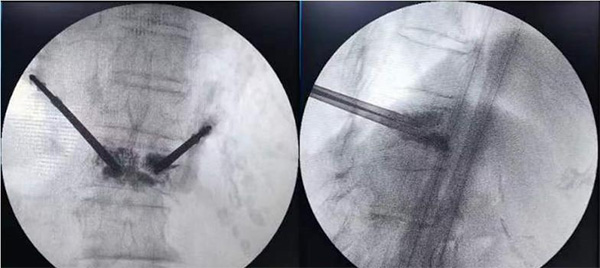

图为术中透视监测下“骨水泥”注射